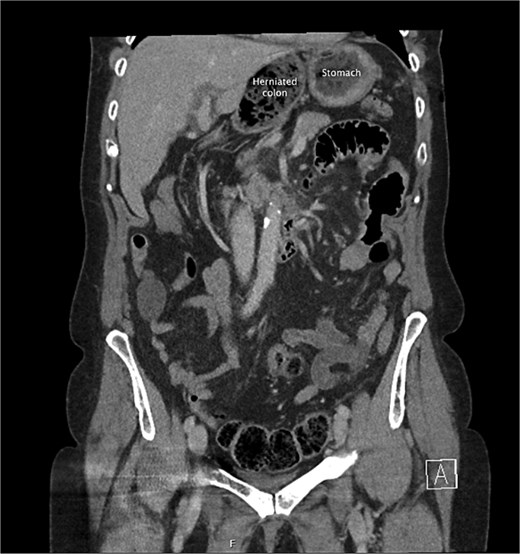

She had a computed tomography (CT) abdomen and pelvis in the emergency department, which was initially reported as mesenteric panniculitis. She had an initial lactate of 3.3 mmol/l (reference range < 2.0), other blood tests, including white cell count and hemoglobin level, were normal. C-reactive protein was also normal. She was referred to the surgical team in the morning to determine a follow-up plan as her pain had improved and she was planned to be discharged home. On review by the surgical team, she was clinically well, her abdomen was soft and not tender on examination. However, on review of the CT images, there appeared to be a dilated segment of colon in the right upper quadrant, and on further analysis, it appeared to be a Foramen of Winslow hernia containing colon. There was also an area that appeared to demonstrate a potential filling defect in the portal vein along with periportal oedema. This raised the concern of a potential thrombus versus vascular congestion (Figs 1 and 2).

A coronal slice from the pre-operative CT abdomen pelvis in portal venous phase, with text labeling the herniated colon and differentiating this from the stomach.